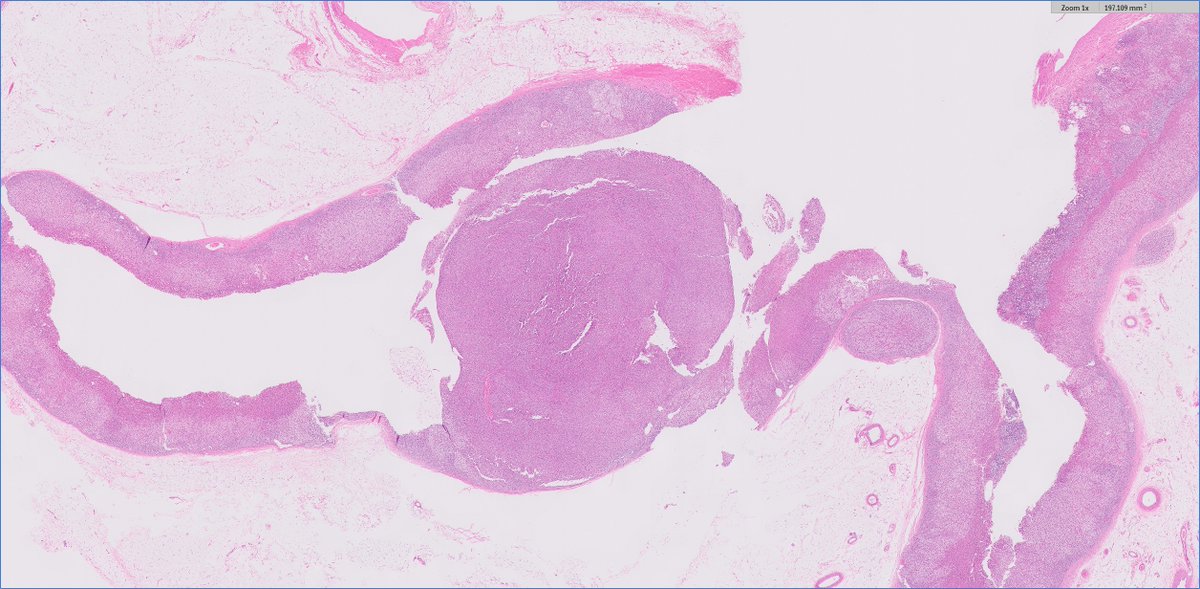

____ Follicular Variant Papillary Thyroid Carcinoma A) Non-invasive encapsulated B) Invasive encapsulated C) Invasive D) None of the above 🔬dpa-dapa.com/public/display… #EndoPath #ENTPath #PathTwitter #PathResidents

DrCycloPath's tweet image. ____ Follicular Variant Papillary Thyroid Carcinoma

A) Non-invasive encapsulated

B) Invasive encapsulated

C) Invasive

D) None of the above

🔬dpa-dapa.com/public/display…

#EndoPath #ENTPath #PathTwitter #PathResidents